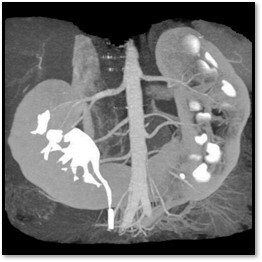

10

Q

What pathology is seen here?

A

Ectopic Kidney